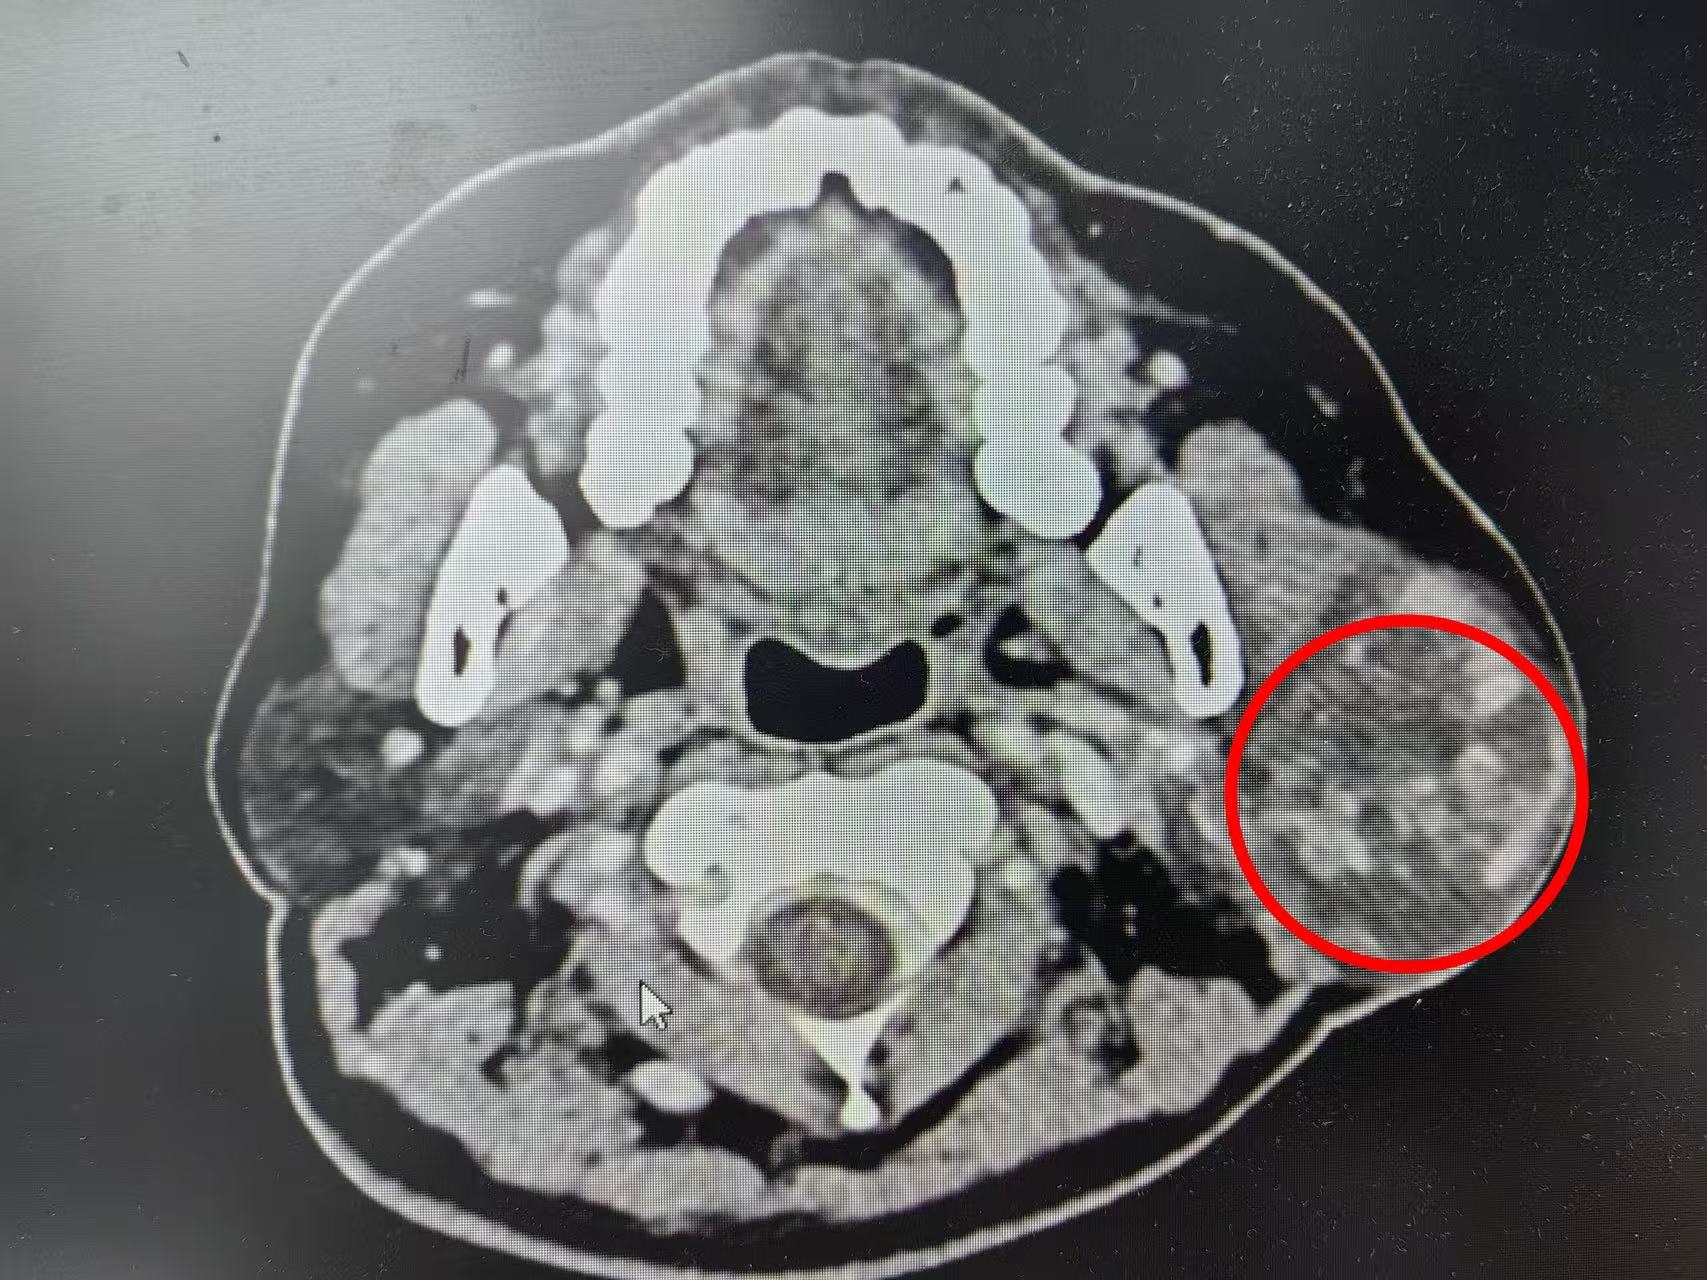

耳鼻咽喉科副主任熊子云接诊后,详细询问病史并仔细查体,为其完善相关针对性检查。腮腺增强CT及超声检查提示,老人腮腺内有一枚约5.3×4.5cm的实性占位,与周边组织粘连较严重,考虑为“腮腺混合瘤”。

这是中老年人常见的腮腺良性肿瘤,但黄爷爷的肿瘤体积巨大,且与面神经分支紧密粘连。若要避免术后面瘫,手术既要完整剥离病灶,又要保护密布其间的面神经,难度极大,对术者的解剖功底与操作精度均有着极高要求。

术中,副主任熊子云与印爱军副主任医师、祁宇扬医师为患者实施“左侧腮腺巨大肿物切除+腮腺部分切除+面神经解剖术”。手术团队精细操作,在高倍显微镜下分离、定位下颌缘支后,逐一分离面神经分支,小心避开血管与周围组织,精准剥离肿瘤。经过2小时奋战,完整切除直径约5cm的巨大肿物,且完美保留了面神经功能,实现了“除瘤不毁容、护神保功能”的目标。